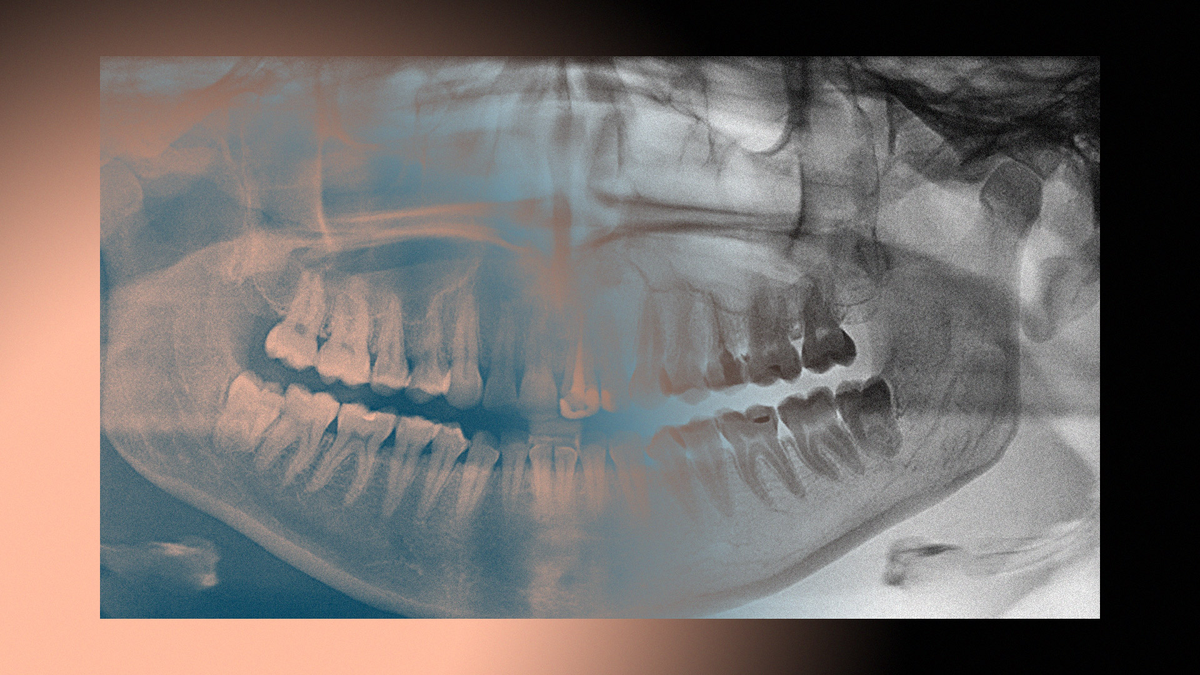

Почему у нас так все плохо с зубами